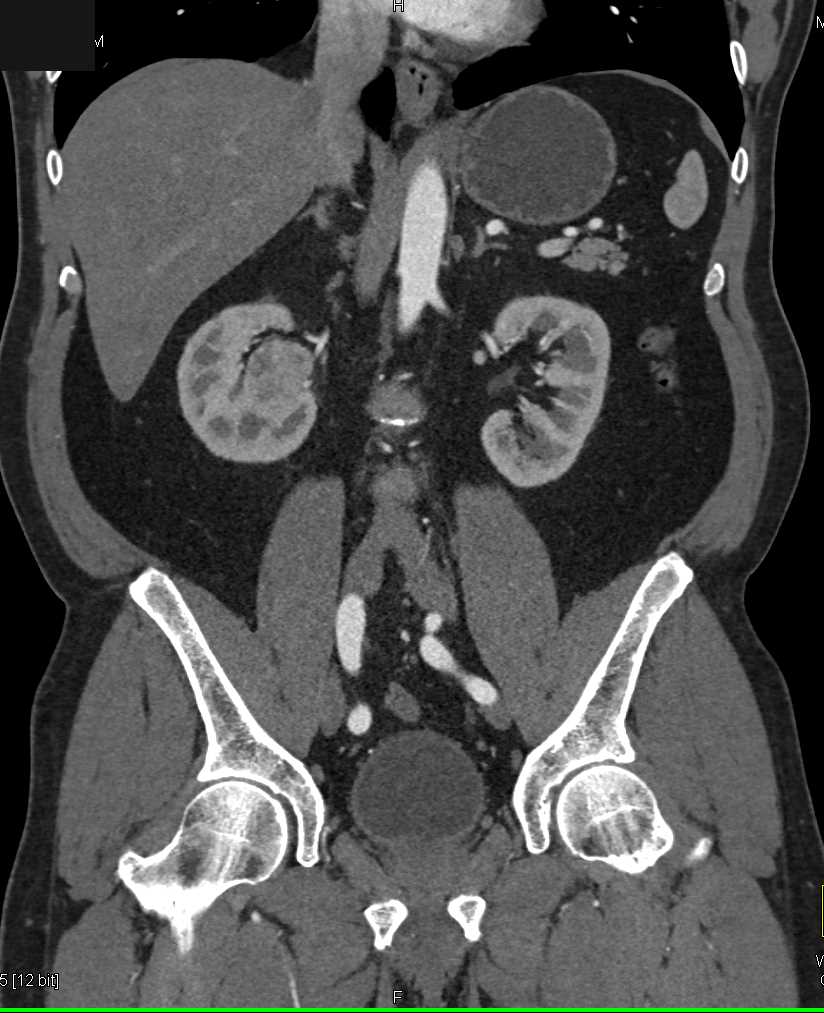

Transitional Cell Carcinoma Right Kidney